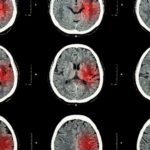

[su_box title=”Keep in mind…” style=”default”] For most of your eye care needs, you will need vision coverage in addition to your basic medical coverage Health insurance does not cover routine eye exams, lenses, or contacts for adults Health insurance will cover most major eye disorders such as glaucoma or diabetic Read more…